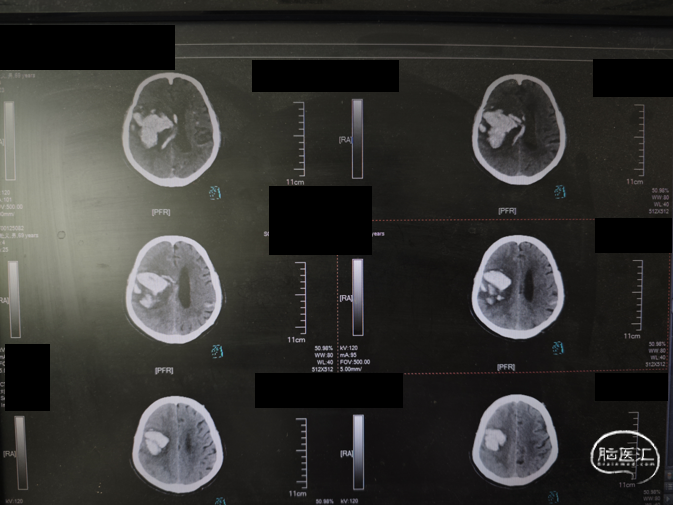

影像所见:右侧脑出血并破入脑液腔系统治疗后复查,右基底节区示团块状高密度影,直径约5.5cm,同恻脑室及双侧脑沟多发高密度铸型改变,中线结构向对侧移位约1cm。

影像提示:右侧脑出血并破入脑液腔;考虑脑疝;建议结合临床。

治疗:脑室穿刺,对侧脑血肿引流。

术后CT